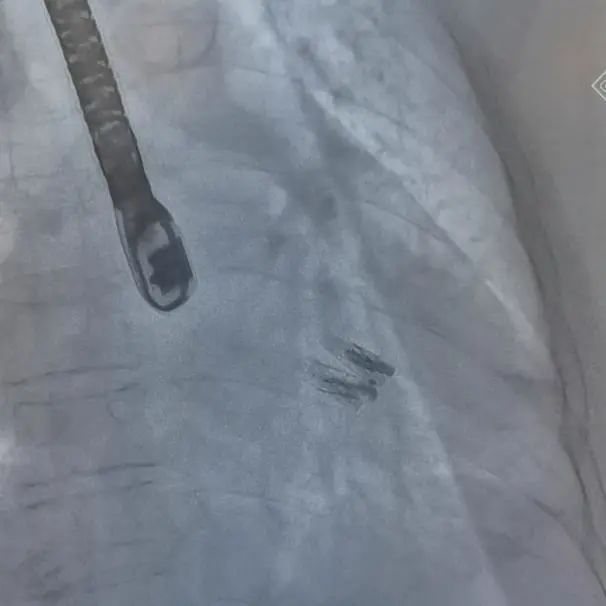

手术过程:4位患者在麻醉科团队保驾护航下,器械经股静脉穿刺房间隔,通过输送系统送入左心房,到达二尖瓣膜反流处,在经食道超声心动图及DSA引导下,术者通过反复评估二尖瓣膜脱垂范围、抓捕位置、返流程度,精准夹合,成功植入DragonFly瓣膜夹(其中3位患者各植入1枚,1位患者植入2枚瓣膜夹)。术后即刻患者返流显著减小、左房压下降,肺静脉逆流减轻,血流动力学改善明显。术后第1天即可自主下床活动,气促等心衰症状较前明显改善。

DragonFly二尖瓣瓣膜夹释放